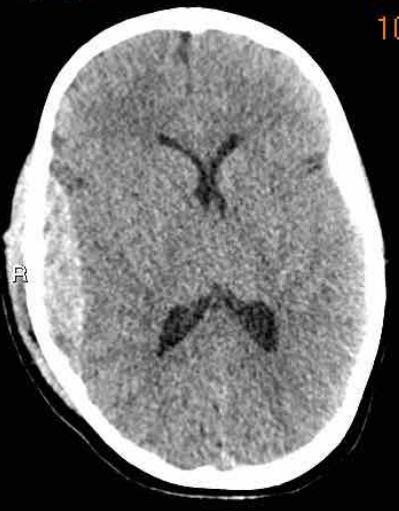

下图 一位46岁的男子骑摩托车时受伤。

瞳孔无反应性,瞳孔扩张。

CT:额叶点状出血。

继续做核磁共振成像

弥漫性轴索损伤(DAI)MRI表现

- 累及皮质下区、胼胝体、右侧丘脑和壳核、脑干、小脑脚和右侧小脑半球。

- 轻度全球萎缩。